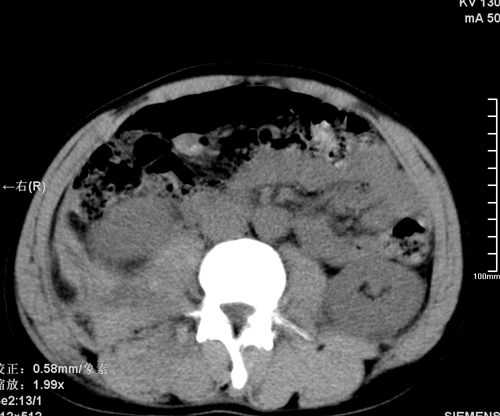

以下是引用qiushi在2008-3-28 12:00:00的发言:[br]腹膜后血肿,所见腰椎横突骨折.[br]建议上传骨窗、腰椎扫描.

以下是引用tao772在2008-3-28 12:29:00的发言:[br]右侧腹膜后积血,右侧腰大肌挫伤,右侧部分横突骨折. 肾脏最好报一下挫伤,必要时增强。